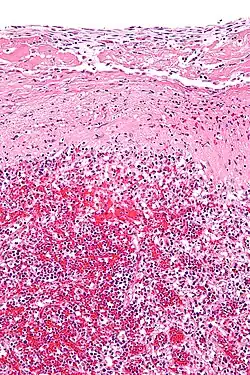

Histopathology

Hyaline cartilage is named after its glassy appearance on fresh gross pathology.[3] On light microscopy of H&E stained slides, the extracellular matrix of hyaline cartilage looks homogeneously pink, and the term "hyaline" is used to describe similarly homogeneously pink material besides the cartilage. Hyaline material is usually acellular and proteinaceous. For example, arterial hyaline is seen in aging, high blood pressure, diabetes mellitus and in association with some drugs (e.g. calcineurin inhibitors). It is bright pink with PAS staining.